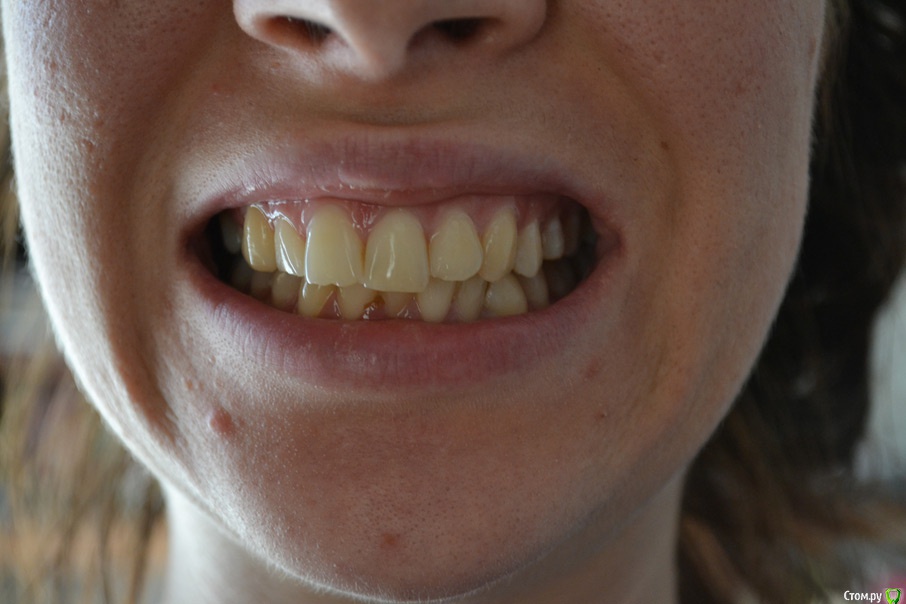

Здравстуйте! Мне 23 года.  У меня смещен центр верхней челюсти вправо и нижней влево. Больше беспокоит меня верх. На верхней челюсти, справа, отсутствует второй премоляр. На нижней клык слева. Премоляр мне в детстве удалили, он рос сверху зуба. Про нижний клык не помню. Проходила лечение не пластинке, не помню, к сожалению, почему. Очень хочу исправить эту ситуацию с зубами, но боюсь решиться, хочется получить гарантию от доктора, что все будет хорошо. Была на 3-х консультациях. На двух сказали что центр сместить нельзя. На одной доктор сказала, что нужно удалить сверху премоляр слева и снизу клык справа. Меня  интересует можно ли это исправить и каким методом, обязательно ли с удалением. Буду очень благодарна за помощь!!

спасибо за ответы! я очень хочу красивую улыбку и, в связи с этим, решительно настроена на лечение. Если кто то может посоветовать мне ортодонта в Москве, буду очень признательна! У себя в Орле я доктора не нашла.